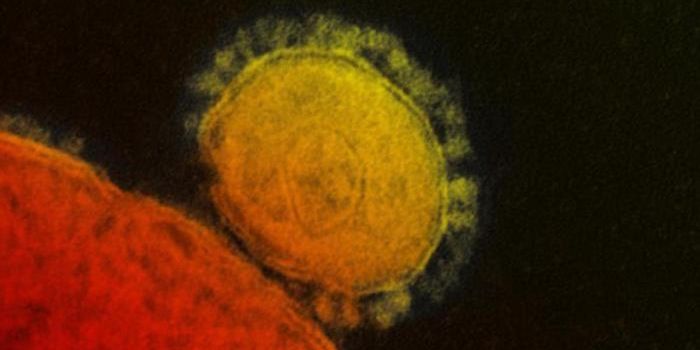

NOV 11, 2021MicrobiologyWhile many people are most familiar with the coronavirus that causes COVID-19, which is called SARS-CoV-2, there are man ...